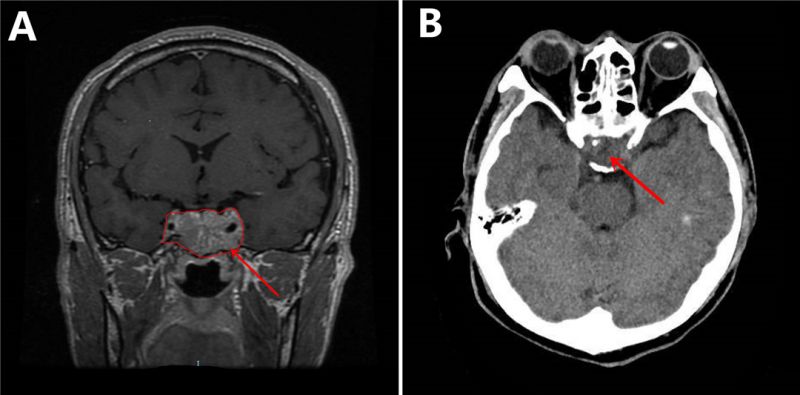

图A箭头所指处为原发肿瘤;图B为术后复查CT,可见肿瘤清除完全。